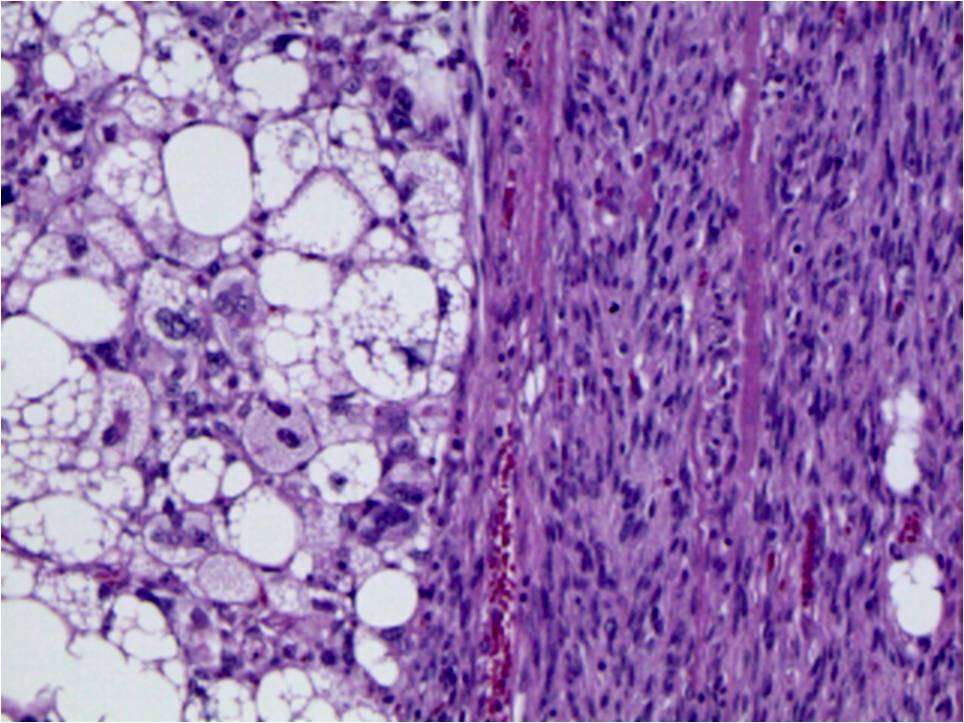

• Well differentiated liposarcoma (Fig. 15) with a sudden transition to a non-lipogenic sarcoma at least in several millimeters (Fig. 16)

Fig. 15 & 16 Microscopic Pathology. Medium magnification photographs demonstrate fibrous bands with enlarged hyperchromatic spindle cells admixed with

adipose tissue corresponding to well-differentiated lipomatous tumor (Fig. 15) and sudden transition between well differentiated liposarcoma to a non-lipogenic spindle cell sarcoma (Fig. 16).